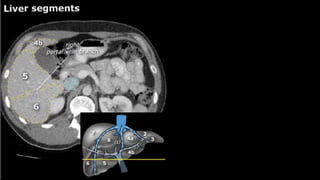

•Liver • A normalliver enhances homogeneously (irrespective of the scan phase). The liver receives about 80% of its blood through the portal vein (= nutrient-rich blood from the intestines). The remaining 20% is supplied by the hepatic artery. y is present, it is important to document its location. This may be crucial to any surgical options. Using the Couinaud classification, the liver is subdivided into eight individually functioning segments. Each segment has its own afferent hepatic artery and portal vein, and efferent hepatic vein and efferent bile ducts

Liver segments Radiopaedia.com1